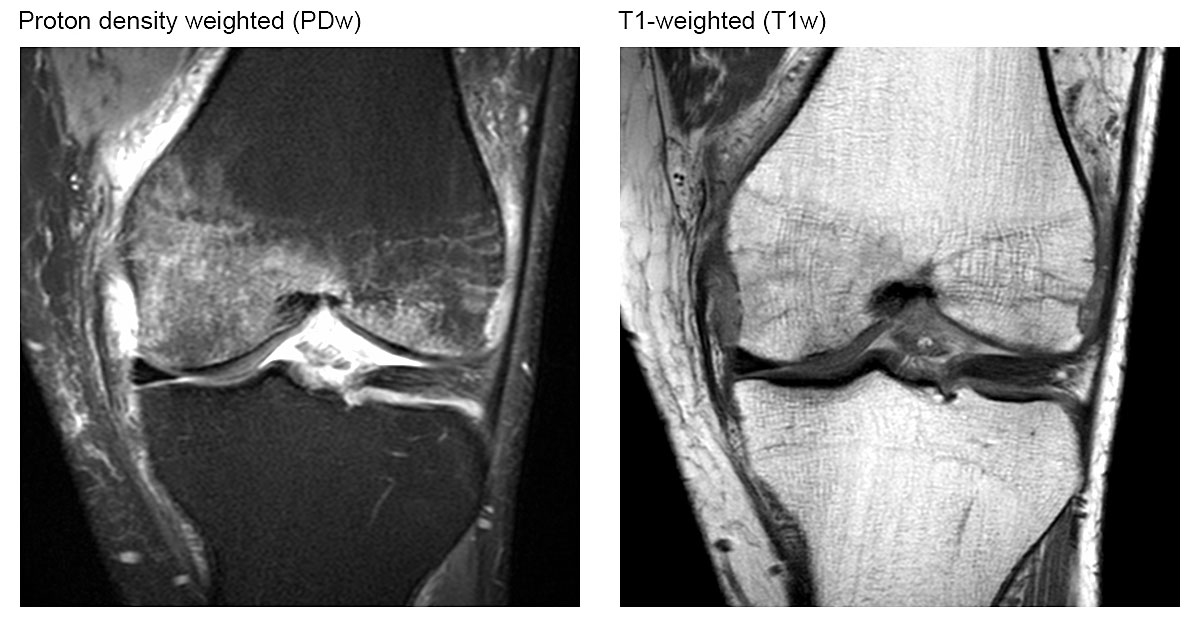

The reason for joint pain often remained unclear before magnetic resonance imaging (MRI) was available, because the findings on X-ray and computed tomography (CT) scans were unremarkable. With the increasing availability of MRI, multiple unspecific alterations can now be detected. These subchondral changes appear with low signal intensity on T1-weighted (T1w) images, and with high signal intensity on fat-suppressed T2-weighted (T2w) or proton density-weighted (PDw) images [1–5], and are called ‘bone marrow oedema’ [4].

The typical diagnostic finding of a bone marrow oedema on a magnetic resonance image is shown in figure 2. The analysis of all magnetic resonance images showed heterogeneous findings (table 2). Overall, 67% of our participants suffered from a subchondral insufficiency fracture. The medial condyle of the femur and the medial part of the tibia head were involved in all cases and the lateral parts were spared. Two thirds of the participants without trauma also had a subchondral insufficiency fracture, which demonstrates that subchondral insufficiency fractures are not necessarily caused by trauma, but also occur spontaneously.

Figure 2 Magnetic resonance imaging appearance of signal changes referred to as bone marrow oedema. Coronal intermediate-weighted MR image with fat suppression illustrating ill-defined high signal intensity in the bone marrow of the medial femoral condyle. Corresponding coronal T1-weighted MR image showing ill-defined hypointensity within the bone marrow. Note: The underlying trabecular structure of cancellous bone is preserved.